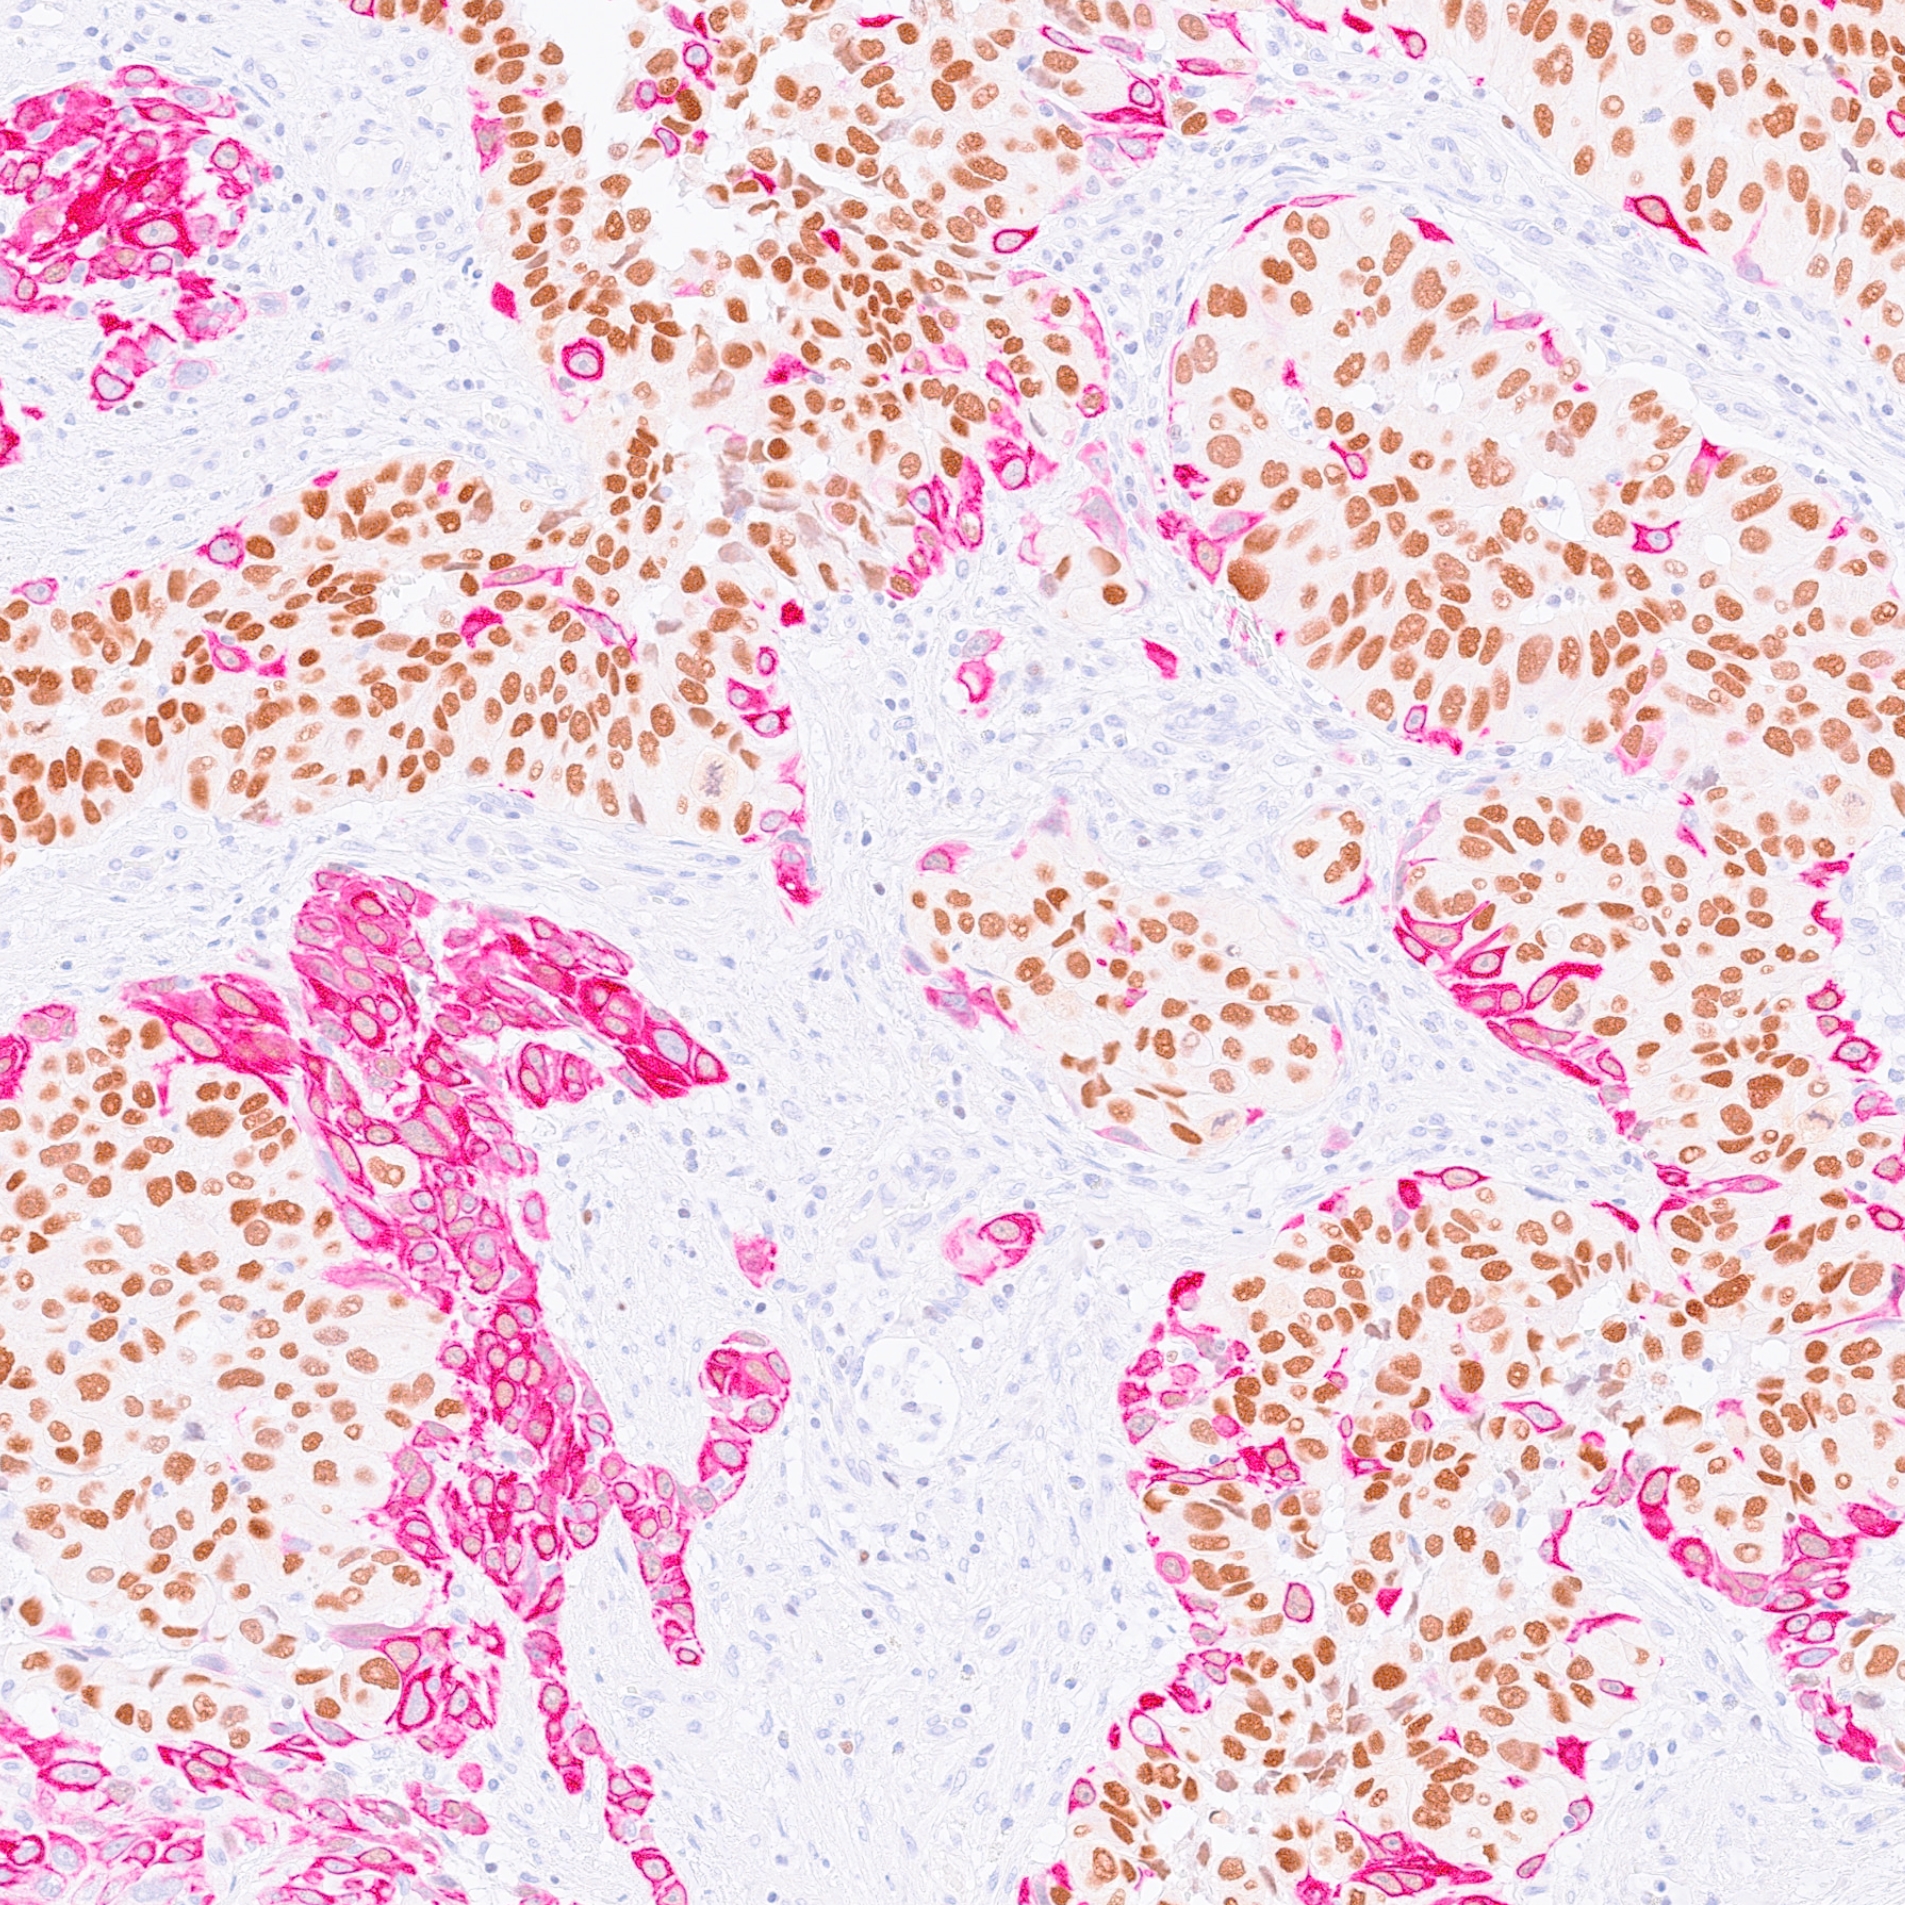

Building on multi-omics strategies that combine genomics, transcriptomics, and proteomics, as well as large-scale bioinformatic analyses and experimental validation in preclinical, cellular, and in vivo models, our work has contributed to the establishment of a molecular classification of muscle-invasive bladder cancers (MIBC), notably distinguishing luminal and basal subtypes with distinct biological, prognostic, and therapeutic characteristics.

This stratification has enabled the identification of subtype-specific oncogenic dependencies, such as activation of the PPARγ/RXRα pathway in luminal tumors and involvement of the EGFR pathway in basal forms, thereby paving the way for precision medicine approaches targeting these vulnerabilities.

Our team has also identified other major alterations, including those involving FGFR3 and the PI3K pathway, and has investigated their impact on tumor biology and the immune microenvironment. We are particularly interested in intra- and inter-patient tumor heterogeneity as well as in mechanisms of treatment resistance, in close connection with clinical data from therapeutic trials, enabling the development and validation of predictive biomarkers of response.